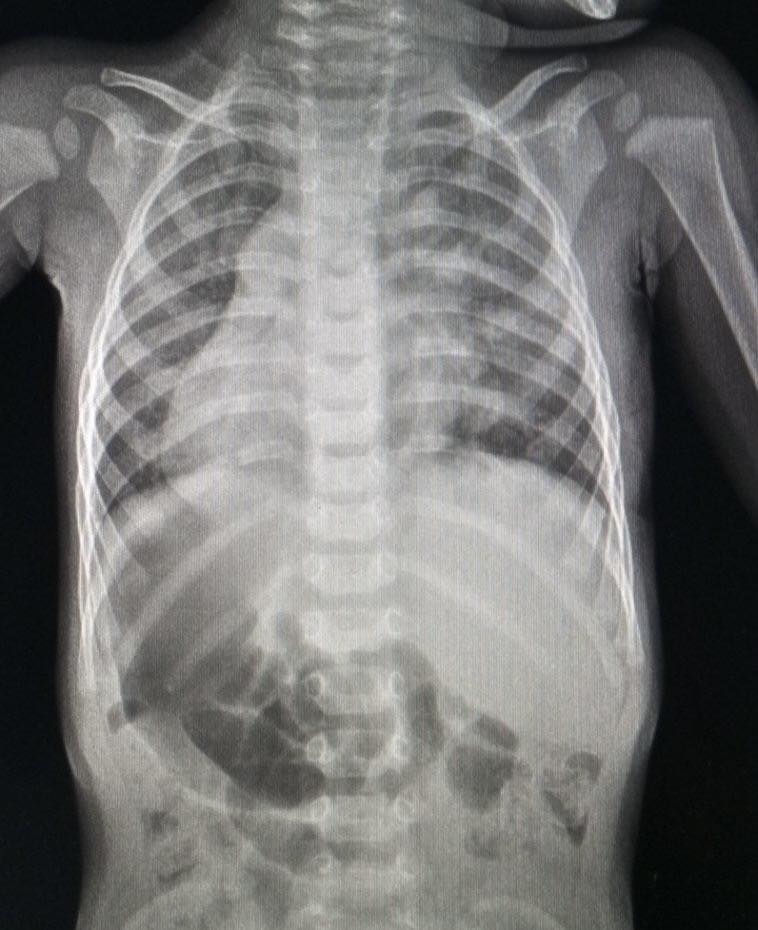

Дем’ян має незвичне розташування внутрішніх органів. Більшість із них розташовані дзеркально. За словами лікарів, таке трапляється вкрай рідко, зазвичай дзеркальне розміщення органів ніяк не впливає на здоров’я і самопочуття.

«Це означає, що його сердечко, селезінка й підшлункова знаходяться справа, а печінка та, скажімо, апендикс навпаки – зліва. Тобто, абсолютно всі органи грудної клітки та черевної порожнини розташовані протилежно», – йдеться в повідомленні.

На дев’ятому місяці життя лікарі виявиои в серці Дем’яна шуми в серці. Медики з’ясували, що в хлопчика є дефект міжпередсердної перегородки із частковим аномальним дренажем легеневих вен. «У нього ці судини впадали не у своє рідне ліве передсердя, а в праве, котре, втім, через дзеркальне розташування органів було фізично розташоване зліва. Така серцева вада в поєднанні з анатомічними особливостями малюка потребувала серйозного оперативного втручання», – пояснили в лікарні.